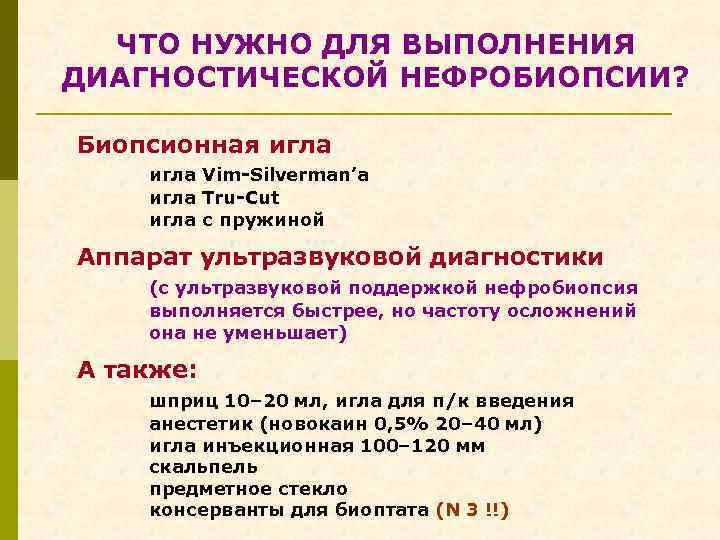

ЧТО НУЖНО ДЛЯ ВЫПОЛНЕНИЯ ДИАГНОСТИЧЕСКОЙ НЕФРОБИОПСИИ? Биопсионная игла Vim-Silverman’a игла Tru-Cut игла с пружиной Аппарат ультразвуковой диагностики (с ультразвуковой поддержкой нефробиопсия выполняется быстрее, но частоту осложнений она не уменьшает) А также: шприц 10– 20 мл, игла для п/к введения анестетик (новокаин 0, 5% 20– 40 мл) игла инъекционная 100– 120 мм скальпель предметное стекло консерванты для биоптата (N 3 !!)